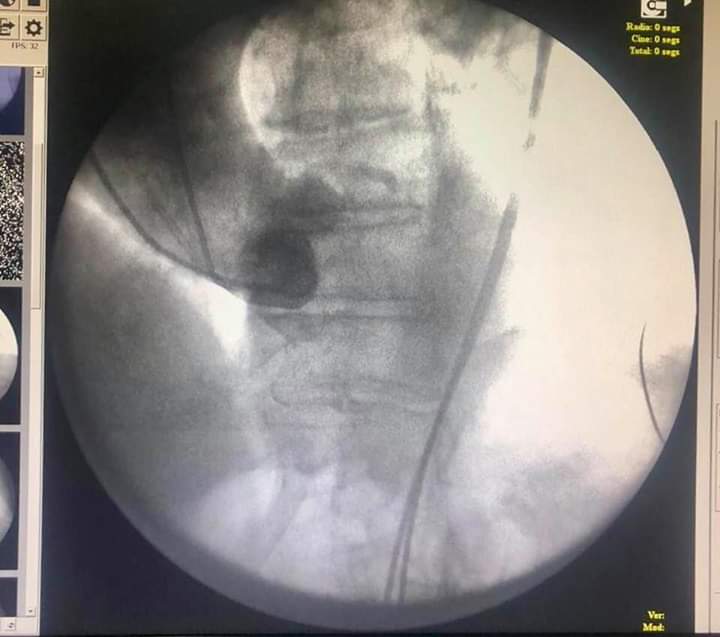

Primer implante de Válvula Aórtica Percutánea (TAVI )Exitoso en el Hospital Rivadavia CABA , gracias a la participación y apoyo de los servicios de Hemodinamia , Cardiología, Cirugía Cardiaca y Vascular , Anestesiólogia , Unidad Coronaria , Ecocardiografía ,Electrofisiología, Enfermería , Instrumentadoras, Radiología y Residentes .